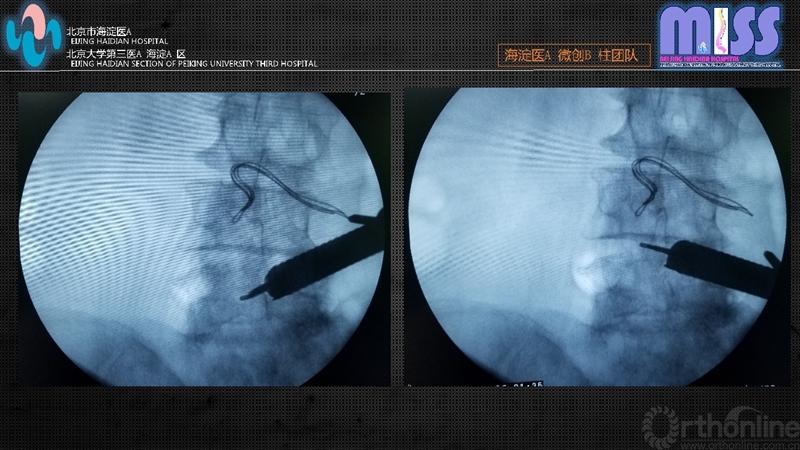

如椎板间隙宽度良好,可采用内窥镜下Kerrison咬骨钳依次对上位椎板下缘、下位椎板上缘及关节突关节进行部分咬除,上下咬除边界为黄韧带止点。如椎板间隙窄,先用动力磨钻磨除增生的上位椎板下缘直至咬骨钳可以操作。外侧增生的关节突关节的切除采用咬骨钳及动力磨钻交替使用,直至扩大到硬膜囊外侧。

骨性结构清理结束后咬除入路侧全部黄韧带暴露硬膜囊,将工作套管向对侧倾斜约20~30°,磨钻适度去除棘突基底部骨质,暴露对侧硬膜及侧隐窝,应用Kerrison咬骨钳咬除对侧黄韧带,磨钻处理对侧增生内聚的上关节突内侧骨质,双侧减压范围:上界为黄韧带止点,下界为椎弓根上缘,外侧边界为神经根或硬膜外缘。术中见硬膜囊膨隆无压迹,神经根无卡压。必要时可采用术中透视确定减压范围。双极射频严密止血后停止灌注,观察有无活动性出血,如无活动性出血,拔出工作套管,缝合皮肤。